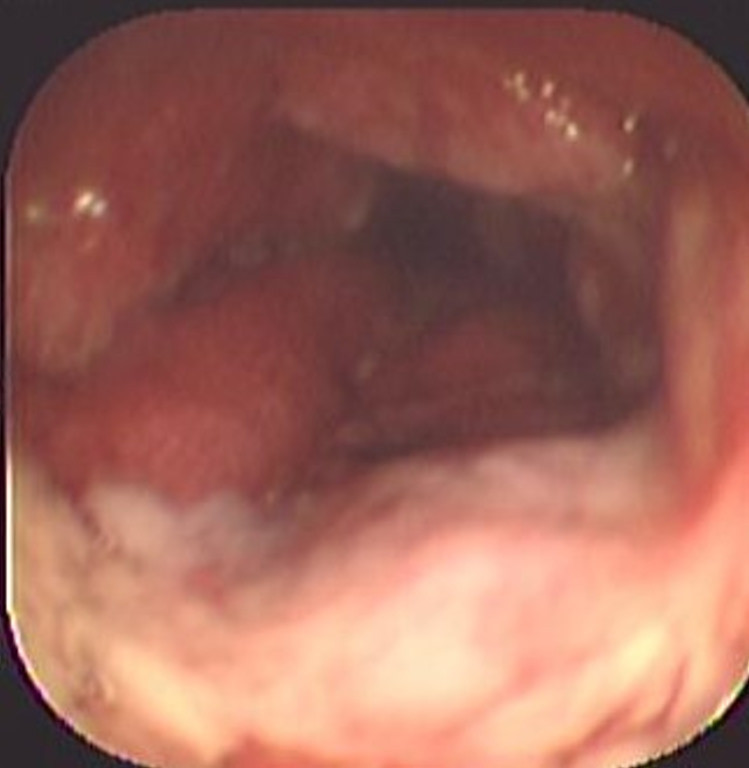

Colitis ulcerosa crónica inespecífica

Envíado por Dr. Carlos Ernesto Arévalo